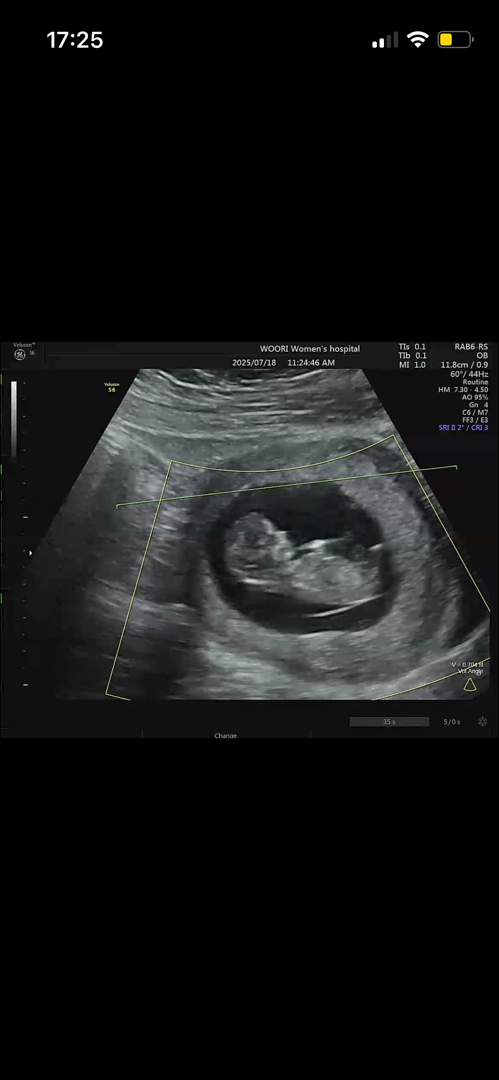

11주차 초음파 뭔가 먹고있어요!

매번 초음파 볼 때마다 안움직여서 슬펐는데 이번에 움직이는 모습 보고 넘 웃겼어요 ㅋㅋ 성별 잘보시는 분들 맞춰주세요❤️ 다음주 금요일날 정답이 나옵니당💕